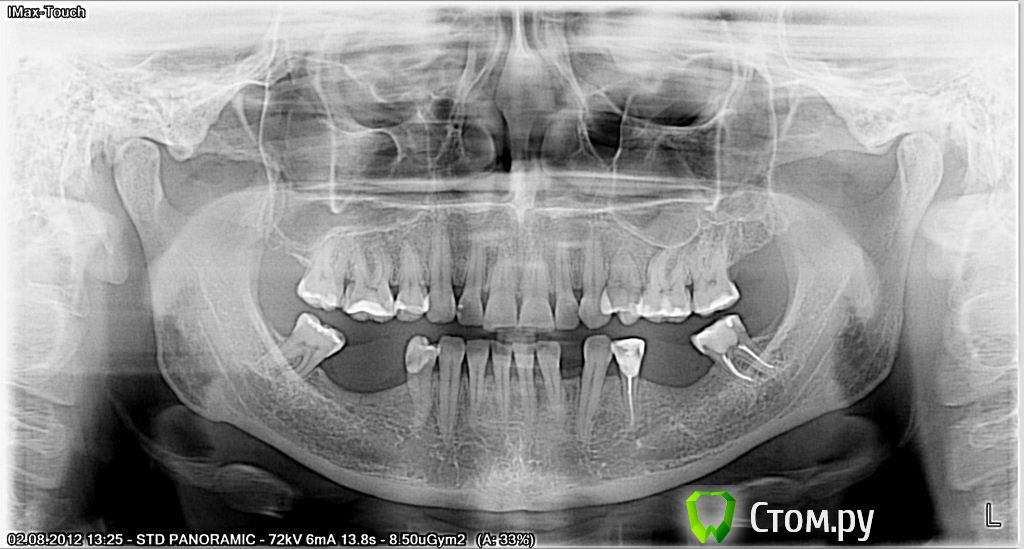

luda77 Опубликовано 19 ноября, 2013 Автор Поделиться Опубликовано 19 ноября, 2013 (изменено) Спасибо за добрые слова. Я немного успокаиваюсь. Вот мои снимки: панорамный до, панорамный месяц назад, фото прикуса и попробую КТ присоединить (весь вечер пыхтела, надеюсь получится) ... Не получилось. Архивировала подпапку, где много файлов. Получилось 21 архивный файл по 1 400-это слишком много. Завтра у умных мужчин на работе спрошу-как. Изменено 19 ноября, 2013 пользователем luda77 Ссылка на комментарий

Ayrat_zub Опубликовано 19 ноября, 2013 Поделиться Опубликовано 19 ноября, 2013 Спасибо за добрые слова. Я немного успокаиваюсь. Вот мои снимки: панорамный до, панорамный месяц назад, фото прикуса и попробую КТ присоединить (весь вечер пыхтела, надеюсь получится) ... Не получилось. Архивировала подпапку, где много файлов. Получилось 21 архивный файл по 1 400-это слишком много. Завтра у умных мужчин на работе спрошу-как.так, а ТРГ вам, я так понимаю, не делали? Ссылка на комментарий

Ayrat_zub Опубликовано 19 ноября, 2013 Поделиться Опубликовано 19 ноября, 2013 (изменено) Спасибо за добрые слова. Я немного успокаиваюсь. Вот мои снимки: панорамный до, панорамный месяц назад, фото прикуса и попробую КТ присоединить (весь вечер пыхтела, надеюсь получится) ... Не получилось. Архивировала подпапку, где много файлов. Получилось 21 архивный файл по 1 400-это слишком много. Завтра у умных мужчин на работе спрошу-как.у вас стекрты резцы и клыки. с верхним зубным рядом, ортодонтиченская работа планировалсь? Изменено 19 ноября, 2013 пользователем Ayrat_zub Ссылка на комментарий